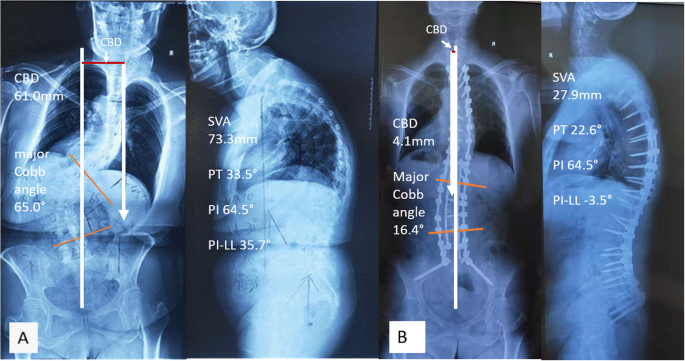

Full-spine standing posteroanterior and lateral radiographs were analyzed preoperatively and post-op 2 weeks or at hospital discharge (Fig. 4a, b). The measurements were done using Surgimap (version 2.2.15; Spine Software, New York, NY) by two independent researchers and the mean values were collected for analysis. The following parameters were measured on the coronal plane: (1) coronal balance distance (CBD), defined as the horizontal distance between the C7 plumb line (C7 PL) and CSVL, C7 PL shifted to the right was defined as positive, and to the left as negative; (2) major Cobb angle. Right curve was defined as positive, left curve as negative; (3) the correction in CBD was defined as ΔCBD, ΔCBD = preoperative CBD- postoperative CBD; (4) the correction in major Cobb angle was defined as Δ major Cobb angle, Δ major Cobb angle = preoperative major Cobb angle- postoperative major Cobb angle. Sagittal parameters included: (1) thoracic kyphosis (TK), the angle between the inferior endplate of T5 and T12, kyphosis was defined as positive, and lordosis as negative; (2) pelvic tilt (PT), a pelvic positional parameter; (3) pelvic incidence minus lumbar lordosis, (PI-LL); (4) sagittal vertical axis (SVA), the distance between C7 PL and posterosuperior corner of S1. (5) corrections in sagittal parameters such as Δ thoracic kyphosis, Δ PT, Δ PI-LL, and Δ SVA, they were defined in the same way as corrections in coronal parameters.

Preoperatively, there were no significant differences regarding CBD, major Cobb angle and imbalance/balance ratio between IGCA and non-IGCA groups (Table 2). After surgery, the CBD in IGCA group was significantly improved from 24.7 ± 20.3 mm preoperatively to 12.6 ± 6.4 mm postoperatively (t = 3.185, p = 0.004), and the imbalance/balance ratio was reduced significantly from 55.6% (15/27) preoperatively to 11.1% (3/27) postoperatively (χ2 = 12.000, p = 0.001). On the contrary, the CBD in non-IGCA group was not improved (17.4 ± 15.1 vs. 18.3 ± 11.4, t = 0.327 p = 0.747)), and the imbalance/balance ratio frustratingly increased from 32% (8/25) preoperatively to 48% (12/25) postoperatively (χ2 = 1.333, p = 0.248). Compared to the non-IGCA group, the amount of correction in CBD (CBD) was significantly larger in the IGCA group (t = 3.274, P = 0.002), and the imbalance/balance ratio in IGCA group was significantly lowered (χ2 = 8.606 p = 0.003) (Table 2). The major Cobb angle in addition to sagittal parameters (SVA, TK, PT, PI-LL) and their changes exhibited no significant differences between IGCA and non-IGCA groups (Tables 2, 3).